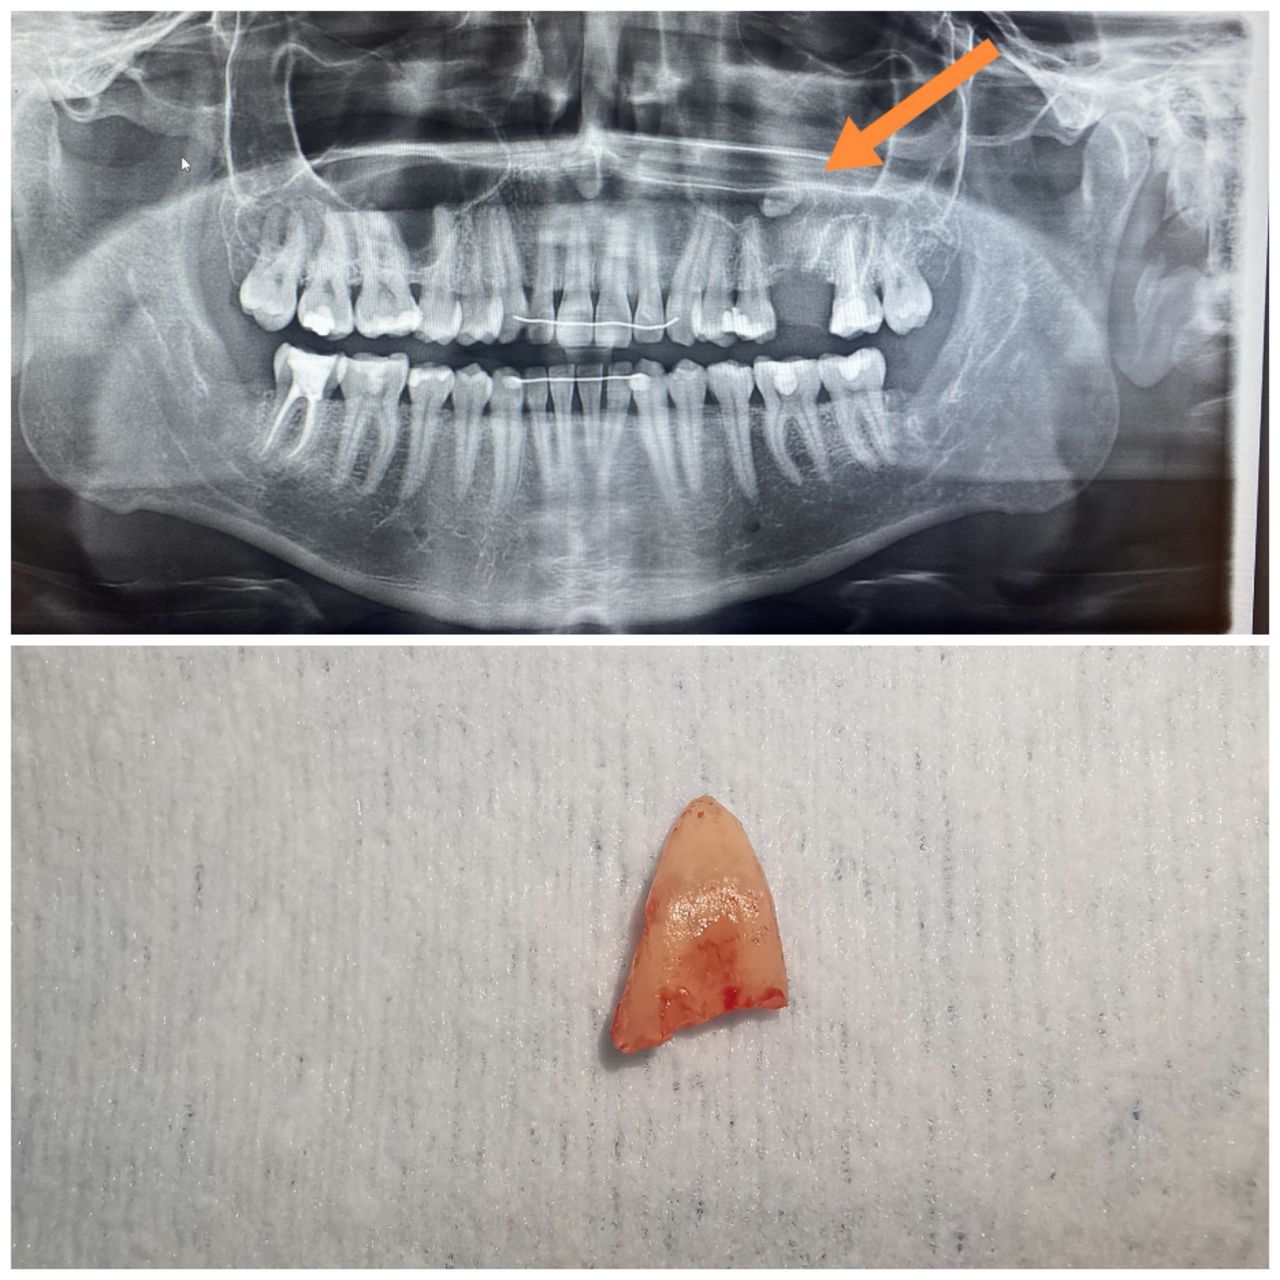

Gömülü Diş Çekimi

Gömülü Yirmi Yaş Dişi Tedavisi

20'lik Diş Çekimi